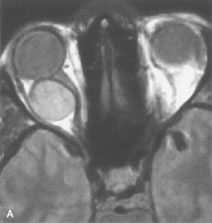

Cavernous hemangiomas appear as well-circumscribed, smooth, usually intraconal masses that are isointense to muscle on T1-weighted images and hyperintense on T2-weighted images (Fig. 12). Patchy early enhancement is typically followed by diffuse, more homogeneous enhancement.39 The internal architecture of the mass, including septation and internal vasculature, may often be appreciated with high-quality orbital imaging.40

Fig. 12. A. T1- and (B) T2-weighted MR scans demonstrate a well-circumscribed intraconal mass causing severe optic nerve displacement. These lesions are usually intermediate in signal intensity on T1-weighted scans and very hyperintense on T2-weighted Images. C and D. Postcontrast fat-suppressed T1-weighted scans demonstrate characteristic patchy intense enhancement that becomes more complete from the initial postcontrast scan (C) to a more delayed scan (D).